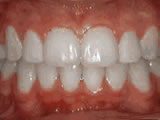

Crowding of the teeth

Patient started treatment at age 11 and wore braces for 26 months. He loves his new smile.